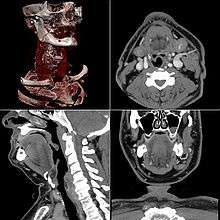

CT produces a volume of data that can be manipulated in order to demonstrate various bodily structures based on their ability to block the X-ray beam. Although, historically, the images generated were in the axial or transverse plane, perpendicular to the long axis of the body, modern scanners allow this volume of data to be reformatted in various planes or even as volumetric (3D) representations of structures. Although most common in medicine, CT is also used in other fields, such as nondestructive materials testing. Another example is archaeological uses such as imaging the contents of sarcophagi. Individuals responsible for performing CT exams are called radiographers or radiologic technologists.[4][5]